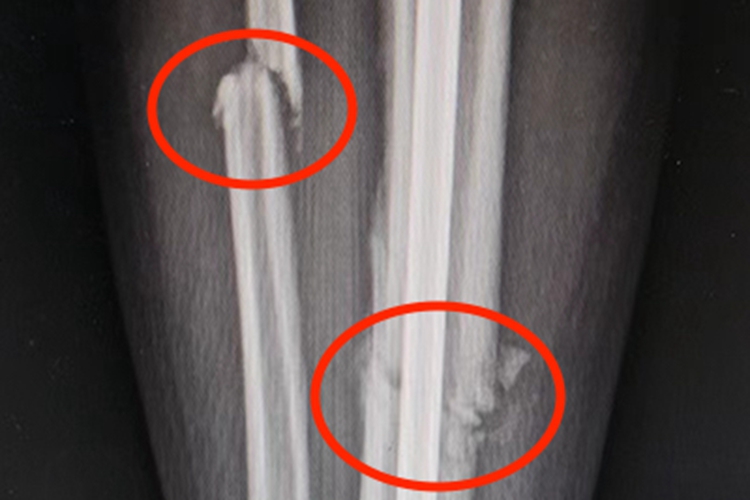

骨折发生在小腿部位时,可造成局部剧烈疼痛,移动患肢时加剧,伴有明显的压痛。部分患者局部存在明显的伤口。X线可见骨的连续性破坏,出现裂纹。

骨折的治疗原则是正确复位,如手法复位和手术复位,同时牢固固定,具体分为内固定和外固定,另外需早期功能锻炼,可以促进骨折局部血液循环,加速骨折愈合,促进功能康复。尽可能做到骨折复位不增加局部软组织损伤,固定骨折而不妨碍肢体活动,使骨折愈合和功能恢复同期完成。